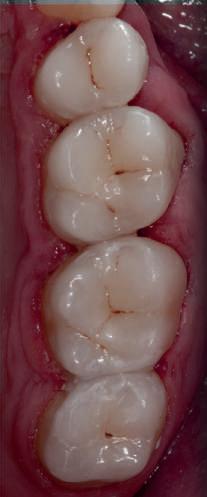

HYBRID COMBINATION RESTAURATIONS

Vonlay-uri: o alternativă conservatoare estetică la coroanele cu acoperire totală